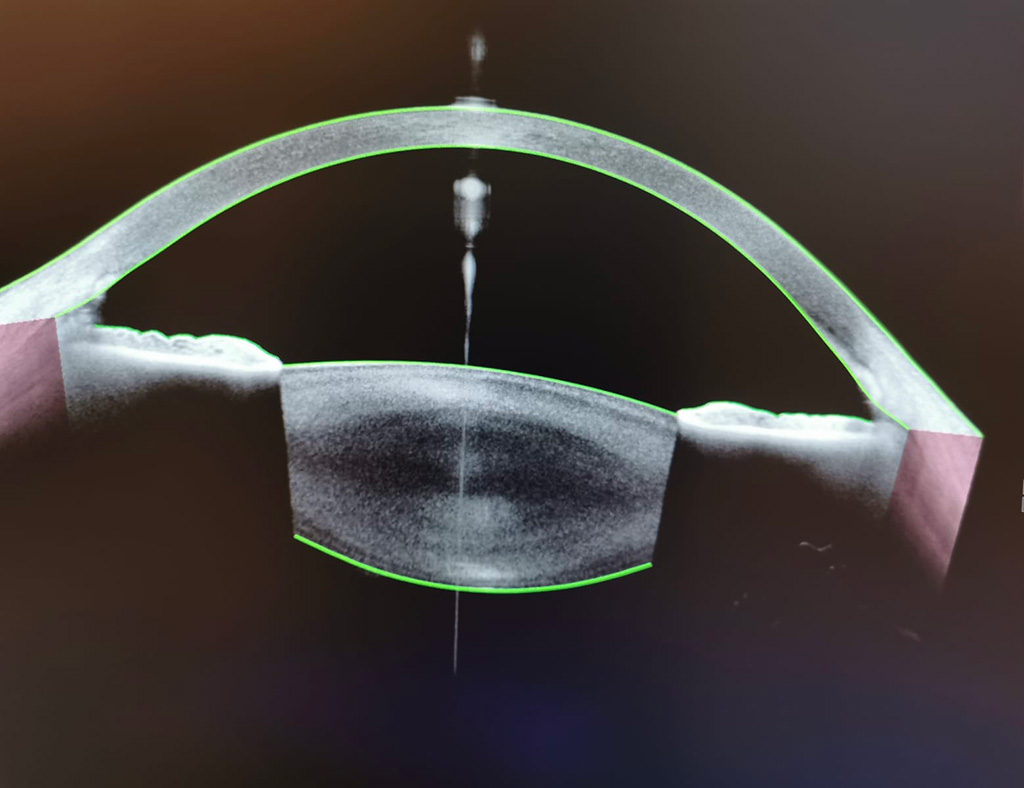

Biometría de última generación

es una técnica avanzada que mide con alta precisión las estructuras del ojo, como la longitud axial y la curvatura corneal. Esto permite seleccionar la lente intraocular ideal para cada paciente, optimizando la visión tanto de lejos como de cerca tras la cirugía de catarata y corrigiendo, si se desea, la presbicia.